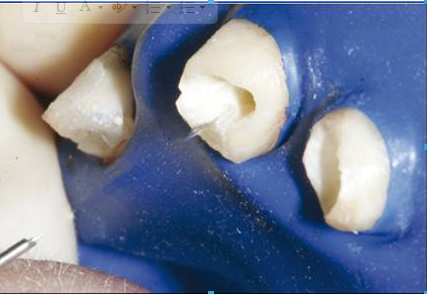

-用橡皮障隔離

2、 試放纖維樁

-務(wù)必使用鑷子夾取纖維樁,防止粘接面被污染,影響粘接強度